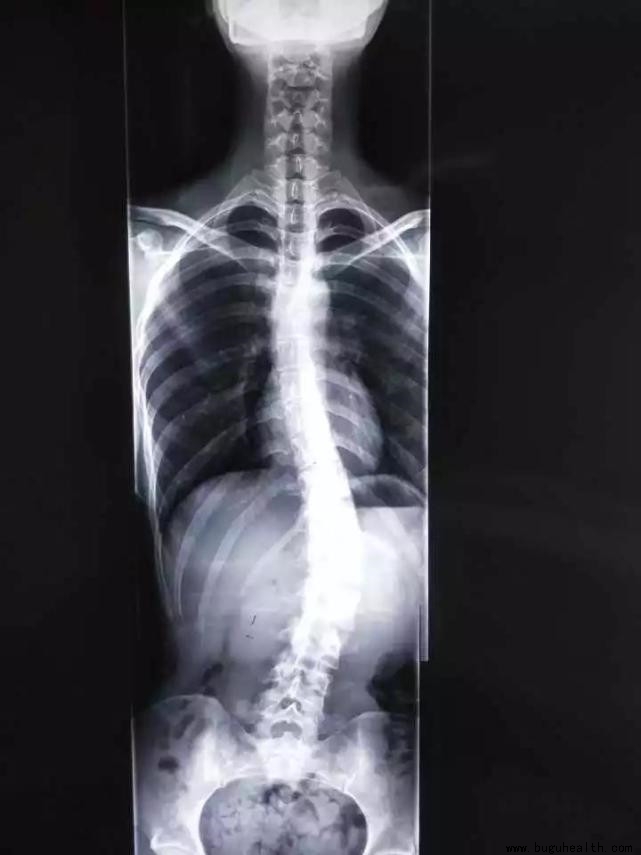

脊柱侧弯|脊柱侧弯危害大,千万不要放任它!

1.什么是脊柱侧弯?脊柱前凸、脊柱后凸、脊柱侧弯。2.脊柱侧弯有哪些危害?影响脊柱外形和功能;影响生理健康;影响心肺功能;影响胃肠系统。3.脊柱侧弯如何判断?根据脊突线判断;根据形态改变判断;根据影像学证据判断。4.脊柱侧弯如何处理? 非结构性脊柱侧凸;结构性脊柱侧凸。5.躯干肌力训练方案:膝跪位腹.....

发现侧弯以后,积极干预还是继续观察?不同的医生给出不同的答案。有的医生擅长手术,对保守治疗并没有深入的研究,有的医生虽然不做手术,但他(她)可能对侧弯的发展有很多经验。.....

青少年特发性脊柱侧凸是一种在未成年人中最常见的三维脊柱畸形,发生于11~18岁之间。青少年特发性脊柱侧凸被认为是影响青少年身心健康的重要疾病,近年来,中国国内各地医疗机构开始逐步落实青少年脊柱侧凸的防治工作。若能从源头抑制或阻止青少年特发性脊柱侧凸的发生发展,则可以更有效地减少该病对未成年人的影响,.....